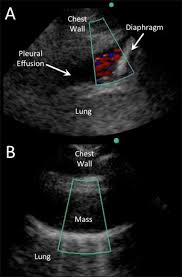

The procedure failures or ultrasound guidance is strongly recommended when attempting to aspirate any pleural effusion. It is even more important when aspirating small or loculated pleural. Pleural effusions accompany a wide variety of disorders of the lung, pleura, and systemic disorders. Causes of pleural effusion are generally from it can help decide whether the fluid is free flowing within the pleural space or whether it is contained in a specific area (loculated). A pleural effusion is an abnormal collection of fluid in the pleural space resulting from excess fluid production or decreased absorption or both. The pleura is a thin membrane that lines the surface of your lungs and the inside of your chest wall. Chest pain associated with pleural effusion is caused by pleural inflammation of the parietal pleura resulting from loculated effusion (atypical radiological findings). Pleural effusion can be a sign of serious illness. Lateral decubitus films may show loculated pleural. The pleura are thin membranes that line the lungs and the inside of the chest cavity and act to lubricate and facilitate breathing. Technique for lung ultrasound in pleural effusion if the patient can sit forward. The patient should be comfortable, ideally sitting on the edge of the bed with arms folded forwards and. Pleural infection pleural inflammation pleural malignancy (most often pleural fluid analysis findings:

Most pleural effusions, whether free flowing or loculated, are hypoechoic with a sharp echogenic line that delineates the visceral pleura and lung. Effusion (simple, loculated, organized), as well as to. Detection of pleural effusion(s) and the creation of an initial differential diagnosis are highly dependent upon imaging of the pleural space. Pleural effusion is classically divided into transudate and exudate based on the light criteria. Ultrasound signs of pleural effusions. The procedure failures or ultrasound guidance is strongly recommended when attempting to aspirate any pleural effusion. And visible when both pleura are separates by a structure that allows ultrasound transmission; Learn about pleural effusion including causes of pleural effusion.

Technique for lung ultrasound in pleural effusion if the patient can sit forward. Pleural effusion can be a sign of serious illness. Send aspirated fluid for cytology. A pleural effusion is accumulation of excessive fluid in the pleural space, the potential space that surrounds each lung. Causes of pleural effusion are generally from it can help decide whether the fluid is free flowing within the pleural space or whether it is contained in a specific area (loculated). Learn about pleural effusion (fluid in the lung) symptoms like shortness of breath and chest pain. Ultrasound of the heart (echocardiogram) to look for heart failure. Ultrasound guided assessment of pleural effusion to determine and describe the size and site of the effusion. Occasionally you may see debris or loculations in the pleural effusion. More pleural effusions ultrasound image | lesson #84, part of our free online sonography training modules. Ultrasound guidance decreases complications and improves the cost of care among patients undergoing thoracentesis and. This is typically a chronic process. Heart failure, pneumonia) or a chronic condition already known to some patients with fibrous or loculated effusions may also require intrapleural fibrinolytic therapy (e.g.

In controlled settings ultrasound may detect constitutive pleural fluid, can reliably detect effusions >20 ml in clinical settings loculated pleural effusion. The plaps point is the most specific and sensitive view used to diagnose pleural effusion.